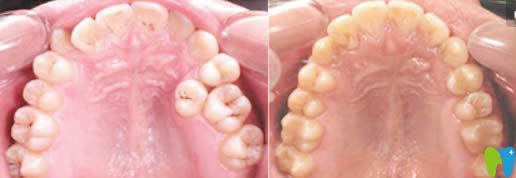

南京佑德口腔傅進(jìn)友主任牙齒正畸效果圖: